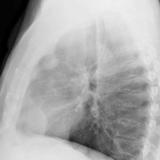

Case 8b Thymoma Lat

Date: 03/27/2009

Views: 14175